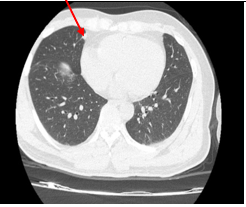

Chụp cắt lớp vi tính lồng ngực: Hình ảnh các nốt kính mờ rãnh liên thùy và màng phổi phải kích thước 2x3mm. Đám dải xẹp phổi thùy giữa phổi phải

Hình 6: Hình ảnh chụp cắt lớp vi tính lồng ngực: nốt tổn thương u phổi phải nhỏ hơn ban đầu sau 3 tháng điều trị (mũi tên vàng)